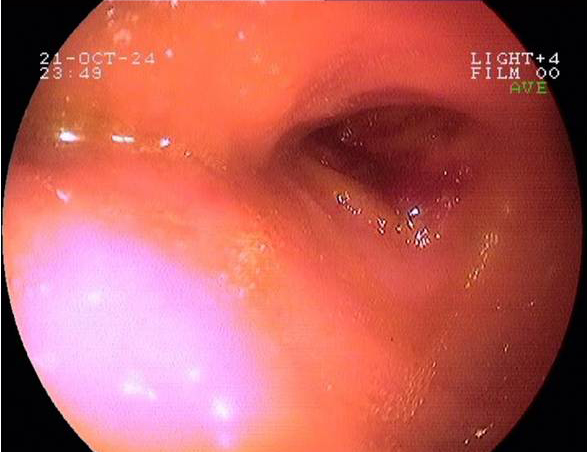

Imágenes tomadas durante la endoscopia digestiva alta y la colonoscopia. Se aprecia una mucosa de aspecto y vascularización normal, sin lesiones visibles. Se progresa con el colonoscopio hasta el íleon. Todo resulta macroscópicamente normal. Se toman biopsias de todos los segmentos explorados.

Pruebas complementarias: panendoscopia oral y colonoscopia

La endoscopia es el método de elección para el diagnóstico y seguimiento de la EII. Permite una visión macroscópica de la mucosa intestinal y la toma de múltiples biopsias para el estudio histológico.

En todos los pacientes en los que se sospeche una EII está indicada la realización de una colonoscopia completa con ileoscopia y una endoscopia digestiva alta.

Es la técnica de elección para diferenciar entre colitis ulcerosa (CU) y enfermedad de Crohn (EC), así como para localizar y valorar la extensión de la enfermedad.

Realizamos una endoscopia digestiva alta y una colonoscopia a la paciente con toma de biopsias, obteniendo el informe de Anatomía patológica.